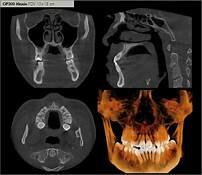

tubos de rayos X: El tubos de rayos X es en el cual se generan los rayos, mediante el cual aceleran electrones y los frena bruscamente y constituye la radiación ionizante

tenia como ventajas a du antecesora la tomografia axial

se creo en 1998 tomografia computarizada multidetector, tambien conocida como multilice

la cual permite ver bien un volumen completo en una sola rotación en su sistema